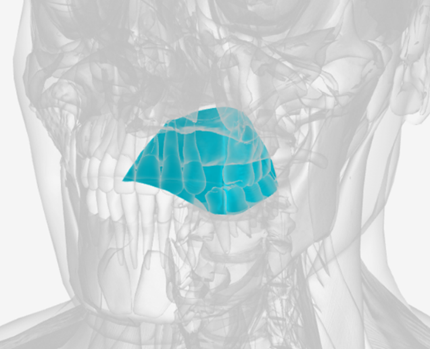

Medial pterygoid

origin is the medial pterygoid plate of the sphenoid bone, coursing down and back to the mandibular ramus; function is to elevate the mandible

Lateral pterygoid

origin is the lateral pterygoid plate and the greater wing of the sphenoid, coursing back to the mandible; function is to protrude the mandible

Medial Pterygoid

|  |  |

Lateral Pterygoid

|  |  |